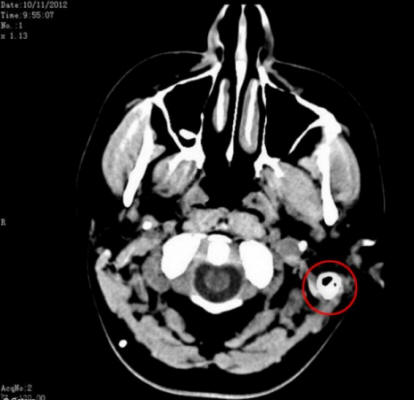

Sam-t számos szakemberre utalták, akik azt gyanították, hogy lehet, hogy agydaganata van. Szerencsére utána egy vizsgálati sorozat elvégzésével az agydaganatot kizárták a betegség lehetséges okainak felsorolása. Az orvosok azonban nem voltak képesek határozza meg, mi történt vele. A szakértők kiderítették az igazat egészségi problémáinak oka csak a derék szúrás.

Az emberi agyat olyan folyadék veszi körül, amely védi az agyat megütötte a koponya falát, de Sam teste kiderült előállítja ezt a folyadékot a normál háromszorosa. Még utána is napi 17 különféle gyógyszer diagnosztizálása és szedése, Sam továbbra is rettenetes fejfájástól szenvedett.